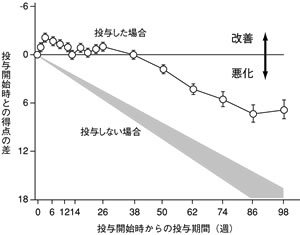

| 図1 アリセプト長期投与中の知的機能の変化(ADAS-cog) |

薬を使わずに何もしないまま経過を見た場合は認知症はどんどん悪くなります。アリセプトを服用すると約1年の「改善期」があり、その後は悪くなっていきますが、その速度はゆるやかです(図1)。薬をやめるとあっという間に悪くなります。

ところで、誰が見てもアルツハイマー型認知症だとわかるような人は、脳内のアセチルコリンを生み出す神経細胞がすでに8割程度も壊れています。こうなると アリセプトの効果も長く続きません。アリセプトはアセチルコリンを生み出すのではなく、残った神経細胞がつくり出したアセチルコリンが分解されるのを遅く する薬だからです。逆に早期のアルツハイマー型認知症(軽度認知障害)の段階から使えば大きな効果が期待できます。早期発見が重要なのです。